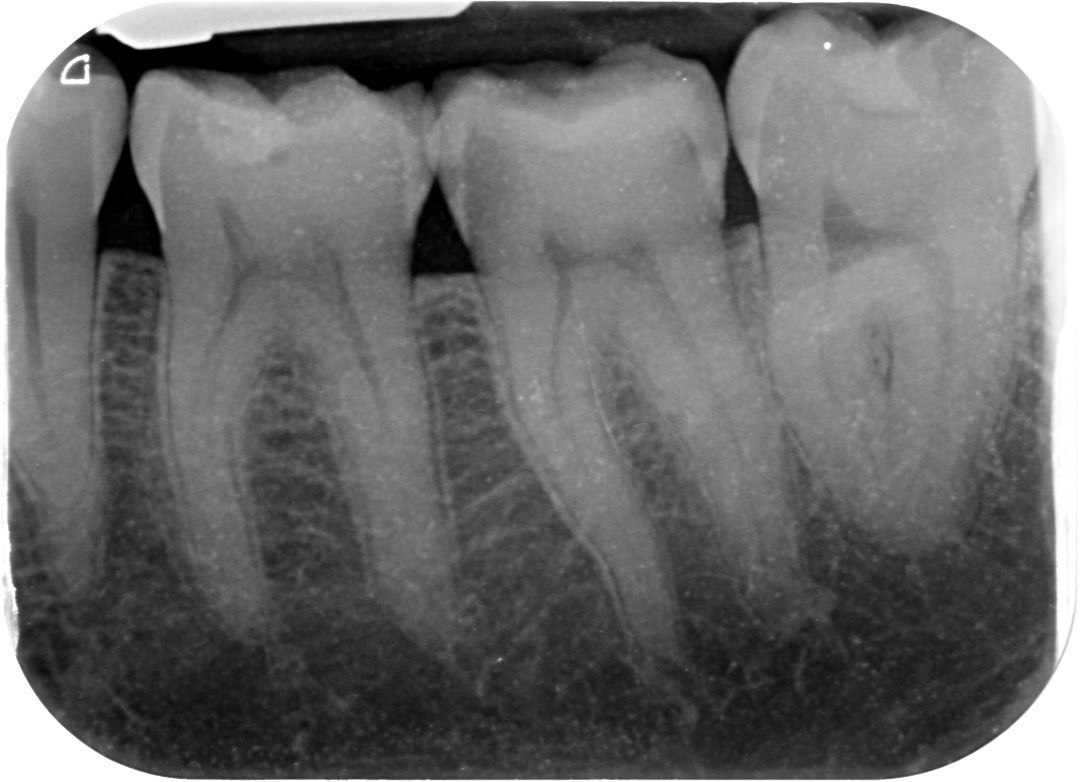

5. Which surface needs restoration?